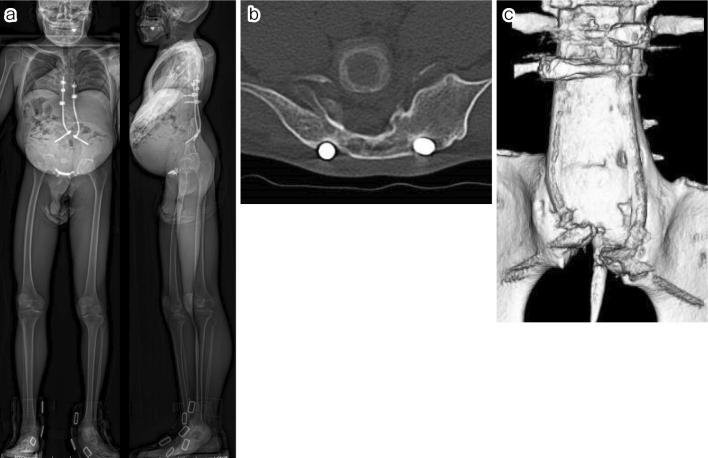

Case 1. A 10-year-old male underwent T8-S posterior fixation followed by multiple augmentations using allografts at the lumbosacral junction for delayed union. All additional procedures with bone graft using a posterior approach failed to achieve bone union; however, additional rigid fixation at the pubic symphysis resulted in a successful lumbosacral bone union. Case 2. A 6-year-old male underwent vertical expandable prosthetic titanium rib (VEPTR) surgery with multiple rod extension procedures. Subsequently, at the age of 10 years, a combined two-stage anterior (L1-3) and posterior (T8-iliac) fixation with T9 hemivertebrectomy was performed. As a result of subsequent nonunion with screw loosening, additional rigid fixation at the pubic symphysis was performed 1 month after posterior fixation. Bone union was finally achieved 1 year after all the surgical interventions.

病例1。一名10岁男性接受了T8 - S后路固定术,随后在腰骶部交界处使用同种异体骨进行了多次增强手术以促进延迟愈合。所有采用后路植骨的额外手术均未能实现骨愈合;然而,耻骨联合处的额外坚强固定导致腰骶部成功骨愈合。病例2。一名6岁男性接受了垂直可扩张人工钛肋骨(VEPTR)手术及多次棒延伸手术。随后,在10岁时进行了两阶段联合前路(L1 - 3)和后路(T8 - 髂骨)固定并进行了T9半椎体切除术。由于随后出现螺钉松动导致不愈合,后路固定术后1个月在耻骨联合处进行了额外的坚强固定。在所有手术干预1年后最终实现了骨愈合。